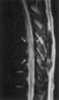

Intramedullary mass

Spinal tumors are neoplasms located in either the vertebral column or the spinal cord. There are three main types of spinal tumors classified based on their location: extradural and intradural (intradural-intramedullary and intradural-extramedullary). [Source: Wikipedia ]